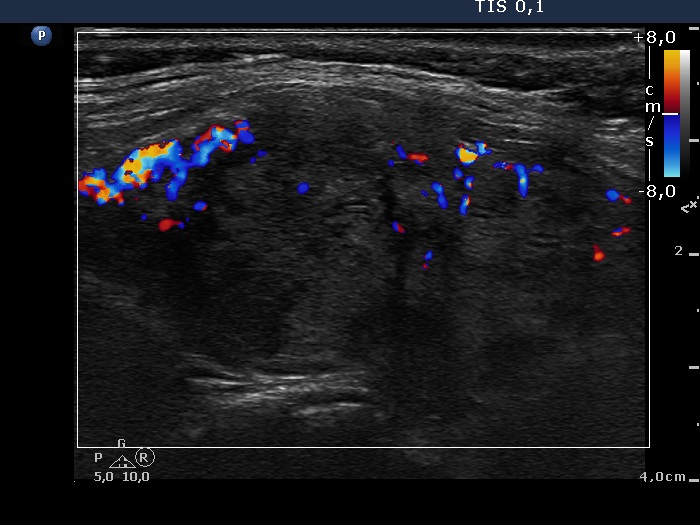

Follow-up examination two years after the first visit (ultrasonographic picture 7)

Left lobe, longitudinal scan, color Doppler mode.